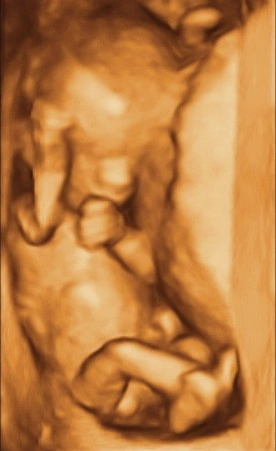

Nuchal Traslucency and/or Early Morphology

This test is done between 12weeks 4 days and 13weeks and 5 days by a Transabdominal scan.

The scan begins with an Early Morphology scan which looks at the heart, brain and other physical features of the baby.

The first trimeser nuchal translucency is a screening programme to find out your chance of having a baby with a major chromosomal abnormalities such as Down's Syndrome . Your doctor may have ordered a NIPT or Harmony test and may not request this part of the test to be done

The test has 2 parts;

1. An ultrasound measures the depth of fluid at the baby's neck called the nuchal translucency. (pronounced as 'new-cal').

2. A special blood test that measures the levels of two hormones- free beta HCG and PAAP-A. The blood test can be done between 10 - 14 weeks. The blood test poses no risk to the baby but you do have to have a needle. We will send you a blood form if you do not have one already. To receive this we will ask you to send a request to info@taraimaging.com.au so we can email it back to you.

At Tara we request that you have the blood test done at least 3 to 4 days before the scan. If you have the blood test done a few days before your scan we should be able to give you your final risk figure after the scan.

The doctor will speak to you personally about your risk and what the numbers mean. If the test places the pregnancy at a high risk of Down's Syndrome you may choose to do more invasive tests to determine if the baby has the condition.